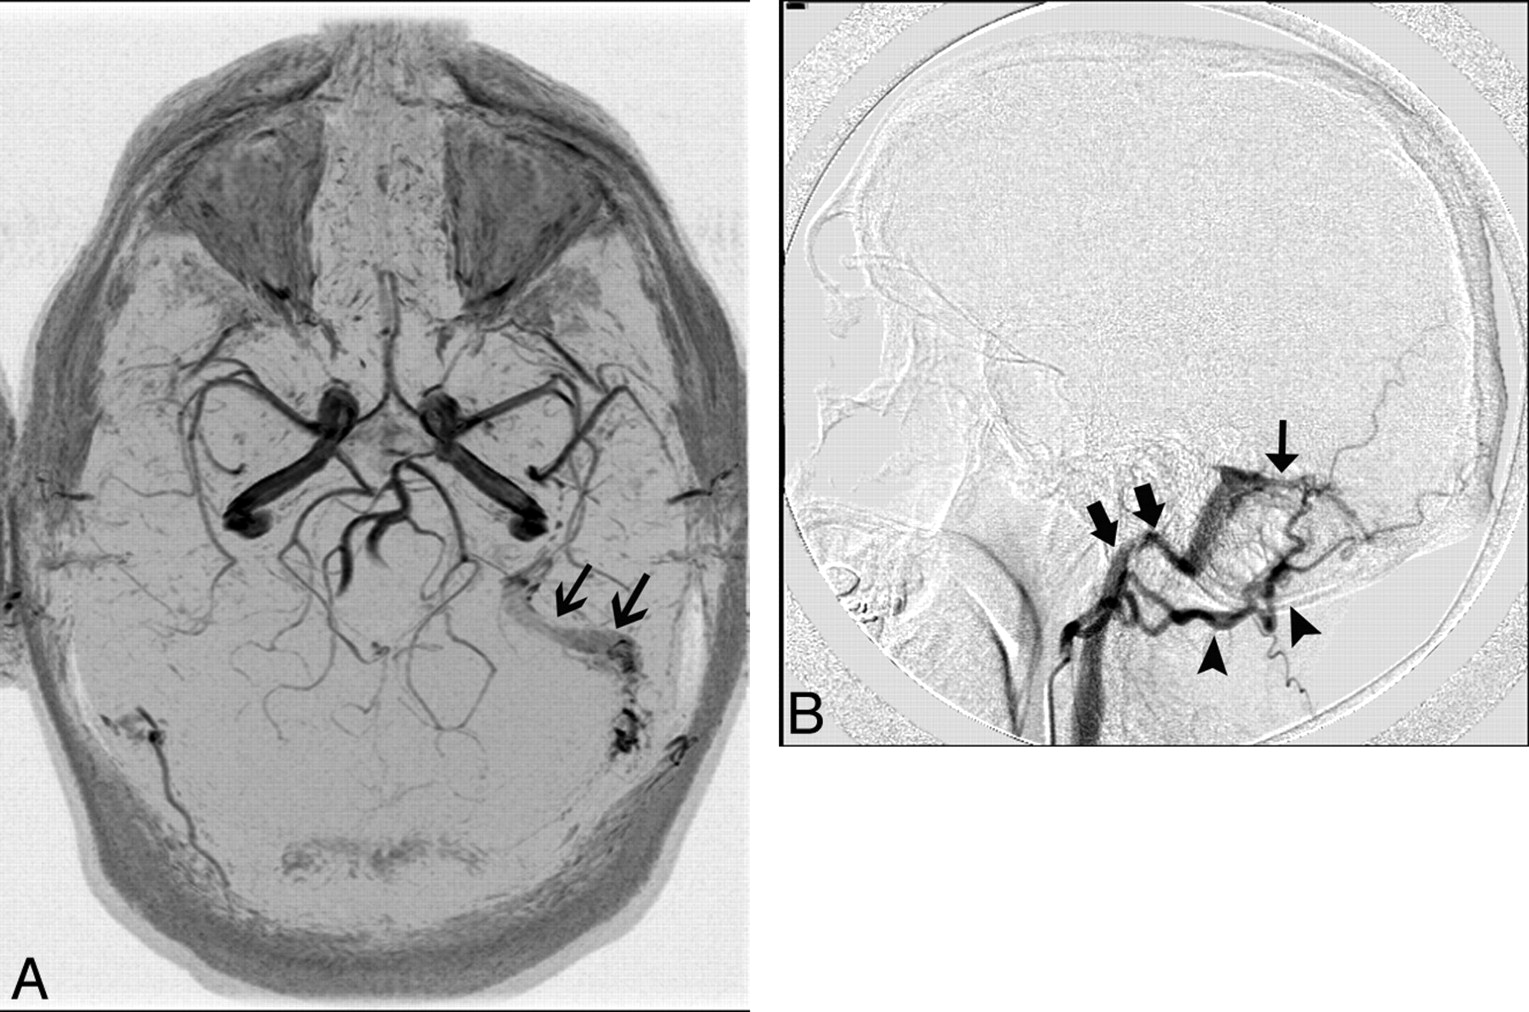

MR imaging findings of AVMs may include flow-void clusters, engorged ophthalmic vein/proptosis, white matter hyperintensities due to gliosis, intracranial hemorrhages, dilated leptomeningeal or medullary vessels, venous pouches, and leptomeningeal or medullary vascular enhancement. MRA findings may include an identifiable fistula, the presence of a venous flow-related enhancement, and the prominence of extracranial vessels (Fig 12A); DSA demonstrates the lesion best (Fig 12B).7,53

A 40-year-old man who presented with left-sided pulsatile tinnitus. A, MR angiogram demonstrates asymmetric increased flow-related enhancement in the left sigmoid sinus (black arrows) and multiple small arterial flow voids within it. B, Lateral projection of DSA shows injection of the left occipital artery (arrowheads) opacifying the AVF (thin black arrow) and rapid opacification of the left sigmoid sinus and internal jugular vein (thick black arrows).